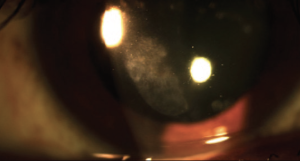

Recurrent corneal erosion is diagnosed through slit lamp examination. Findings range from a normal exam to mild irregularities of the cornea (such as epithelial microcysts) to large areas of loose epithelium or epithelial defects, which can be delineated with fluorescein staining. Intrinsic abnormalities of corneal epithelial adhesions, such as from corneal dystrophies, tend to present bilaterally and symmetrically. In cases of previous trauma, the area of erosion usually corresponds to the location of the previous injury.